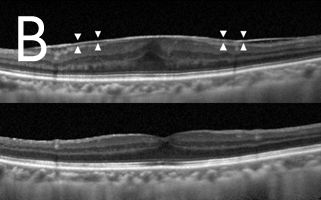

老年性(图4)及深近视性(图5)黄斑点退化的脉络膜新生血管膜之治疗

光动力疗法曾经是老年性及深近视性黄斑点退化的脉络膜新生血管膜的主要治疗,惟此治疗仅可维持已衰退的视力,或遏止视力进一步退化。现时,眼内药物注射(包括Lucentis丶Avastin丶Eylea及类固醇)是常见治疗方法,能让大部份病人回复一定程度的受损视力。而且注射过程安全,甚少出现副作用。